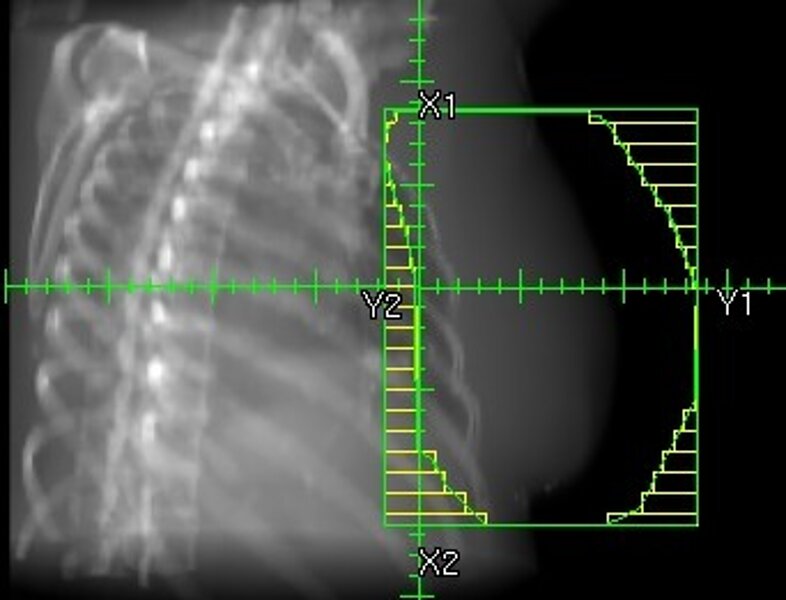

IGRT (Image Guided Radiation Therapy)

3D-bildgeführte Strahlentherapie zur Kontrolle von Patientenlagerung, Blasenfüllung etc.. Nur sehr wenige Kliniken in Deutschland bieten die IGRT an.